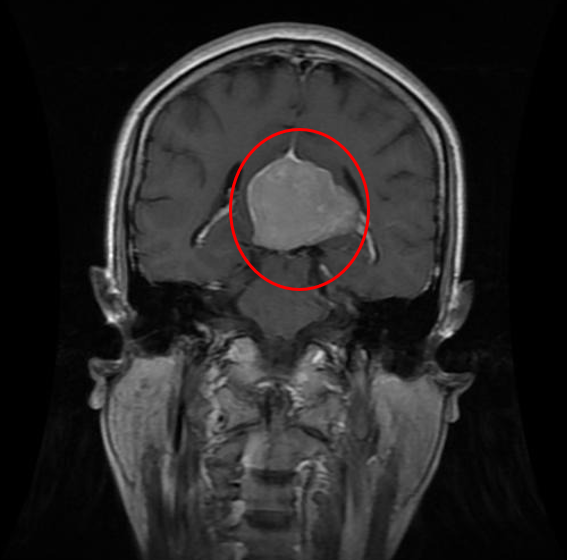

## 2. Meningioma Tumor: A meningioma is a tumor that arises from the meninges — the membranes that surround your brain and spinal cord. Although not technically a brain tumor, it is included in this category because it may compress or squeeze the adjacent brain, nerves and vessels.Pituitary tumors are abnormal growths that develop in your pituitary gland. Some pituitary tumors result in too much of the hormones that regulate important functions of your body. Some pituitary tumors can cause your pituitary gland to produce lower levels of hormones.